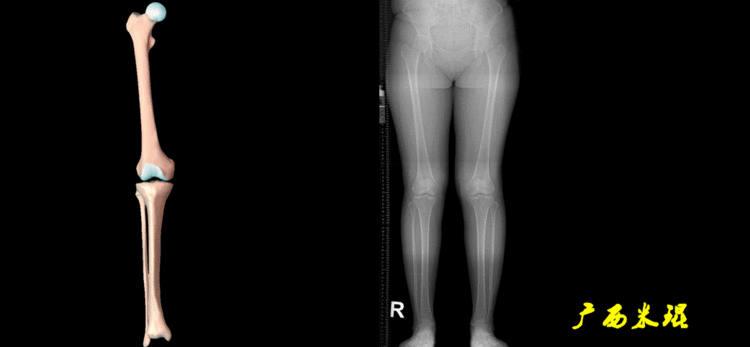

无论如何,拍摄出来的下肢全长片必须包含髋关节中心、膝关节中心及踝关节中心,否则对临床是无用的。有了一张下肢的全长照片,我们需要确定下肢关节的中心点,通过中心点画出下肢的各种轴线,然后利用轴线与关节线的相交得出各种所需要的角度。

2、画出下肢的轴线确定髋关节、膝关节、踝关节的中心点后,我们才能了解下肢的几个轴线。(1)解剖轴股骨和胫骨的骨干中线为解剖轴,股骨解剖轴和胫骨解剖轴的夹角正常值为174°±1°。

(2)机械轴机械轴是连接近端和远端关节中心点的直线。

机械轴要分前后位及侧位,站立前后位(也就是冠状面)股骨头中心与踝关节中心的连线通过膝关节中心,这是下肢的机械轴线,也就是下肢力线,常说Mikulicz线。冠状面的力线评估在临床工作中最常用、最基础、最重要。

开始接触时可能我们对这些轴有点混乱,通过下面的这张图片就能清楚的了解下肢几个轴之间的关系。